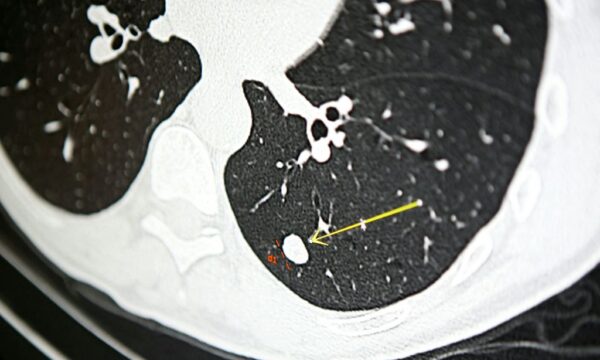

命を救うCT検査 小児がんとの関連を研究が指摘